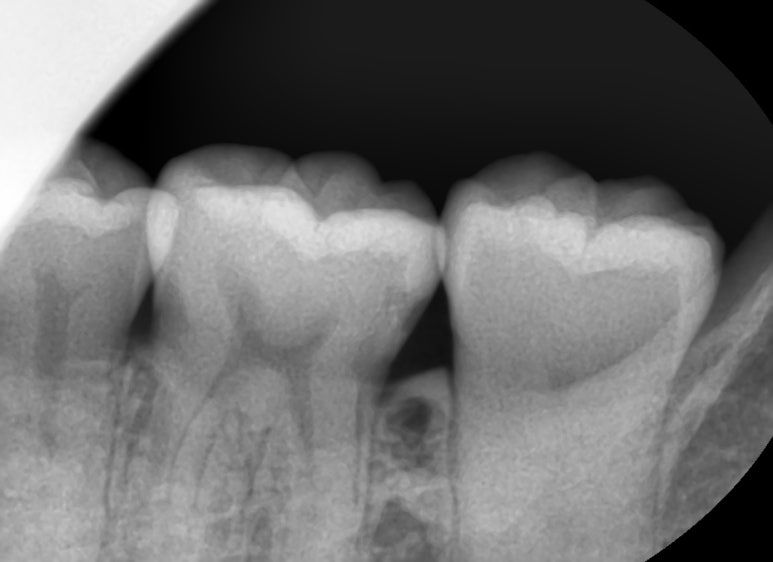

치료 전, 치료 중간 신경치료해야 할 만큼 깊은 충치를 보여드리기 위해 찍은 사진

눈으로 체크 하고 엑스레이로 더블체크하며

크랙을 체크하는 기계,

더 필요한 부분은 3D CT도 촬영할 수 있게 필요한 장비들이 많이 구비되어 있습니다.